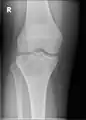

A variety of imaging studies can be used to diagnose chondroblastoma, with radiographs being the most common.[10][8] Laboratory studies are not considered useful.[14] Classical chondroblastoma (appearing on long bones) appears as a well-defined eccentric oval or round lytic lesion that usually involves the adjacent bone cortex without periosteal reaction.[10][13] A sclerotic margin can be seen in some cases.[10][13] For long bone chondroblastomas the tumor is typically contained to the epiphysis or apophysis but may extend through the epiphyseal plate.[10][13] Chondroblastomas are usually located in the medullary portion of bones and can, in some cases, include the metaphysis.[10][13] However, true metaphyseal chondroblastomas are rare and are typically the result of an extension from a neighboring epiphyseal legion.[10][13] Most lesions are less than 4 cm.[10] A mottled appearance on the radiograph is not atypical and indicates areas of calcification which is commonly associated with skeletally immature patients.[10] Additionally, one-third of all cases involve aneurysmal bone cysts which are thought to be the result of stress, trauma or hemorrhage.[10] In cases involving older patients or flat bones, typical radiographic presentation is not as common and may mimic aggressive processes.[10][13]

1. a. X-ray of chondroblastoma of thigh bone near knee -

1. b. CT scan shows chondroblastoma of thigh bone near knee more clearly -